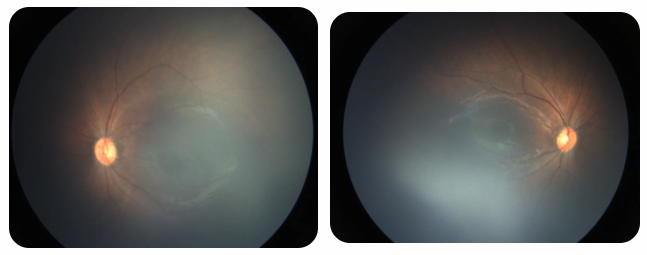

廈門眼科中心黎曉新名醫(yī)工作室曾接診一名31周出生的早產(chǎn)兒,出生體重僅1300克。由于家長缺乏篩查意識,直到孩子5個(gè)月大時(shí)眼睛仍不會(huì)追光,才前來就診。檢查發(fā)現(xiàn),患兒ROP已進(jìn)展至4B期,因纖維血管增殖牽拉導(dǎo)致視網(wǎng)膜脫離,錯(cuò)過了最佳治療窗口。盡管黎曉新教授團(tuán)隊(duì)成功實(shí)施了玻璃體切割手術(shù),孩子的視力仍存在不可逆損傷。此后,孩子開啟了長期隨診復(fù)查、治療的“護(hù)眼征程”,目前其右眼矯正視力為0.6,左眼為0.8。

近期術(shù)前檢查:

早產(chǎn)兒視網(wǎng)膜病變

術(shù)后復(fù)查:

相比之下,另一位早產(chǎn)寶寶在出生5周后,生命體征穩(wěn)定之時(shí),便在產(chǎn)科醫(yī)生的建議下轉(zhuǎn)診至廈門眼科中心。經(jīng)篩查確診為Ⅲ期ROP,黎曉新教授團(tuán)隊(duì)及時(shí)為其進(jìn)行了激光治療。半年后復(fù)查顯示,寶寶的視網(wǎng)膜血管發(fā)育正常,視力發(fā)育與足月兒童無異。